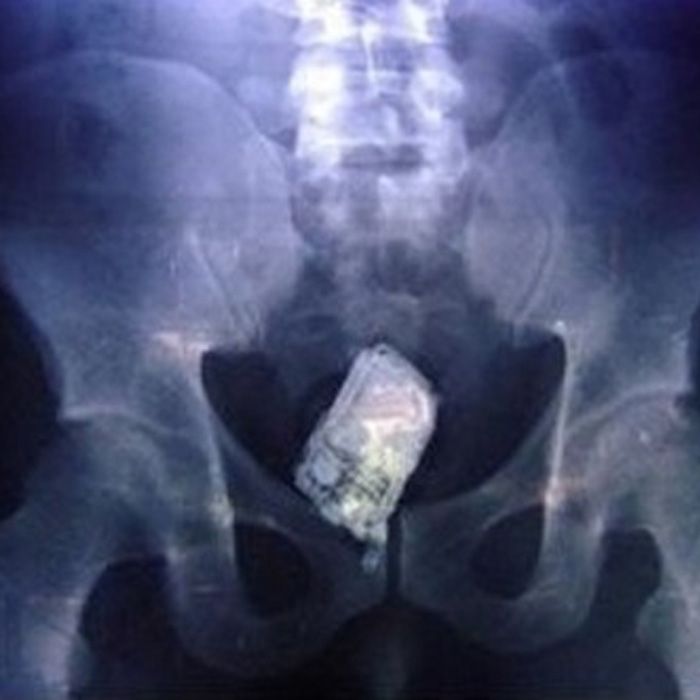

A cell phone – this is certainly “talking out of your ass.” Yes, I went there. Sue me.